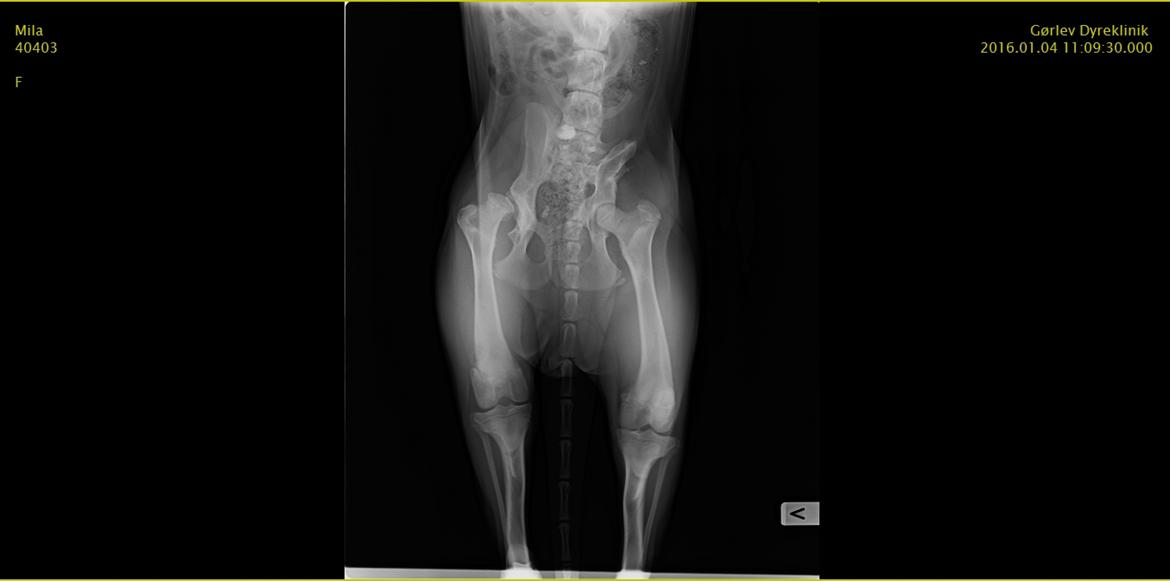

Schæferhund Mila - Hendes røngten  billede 15